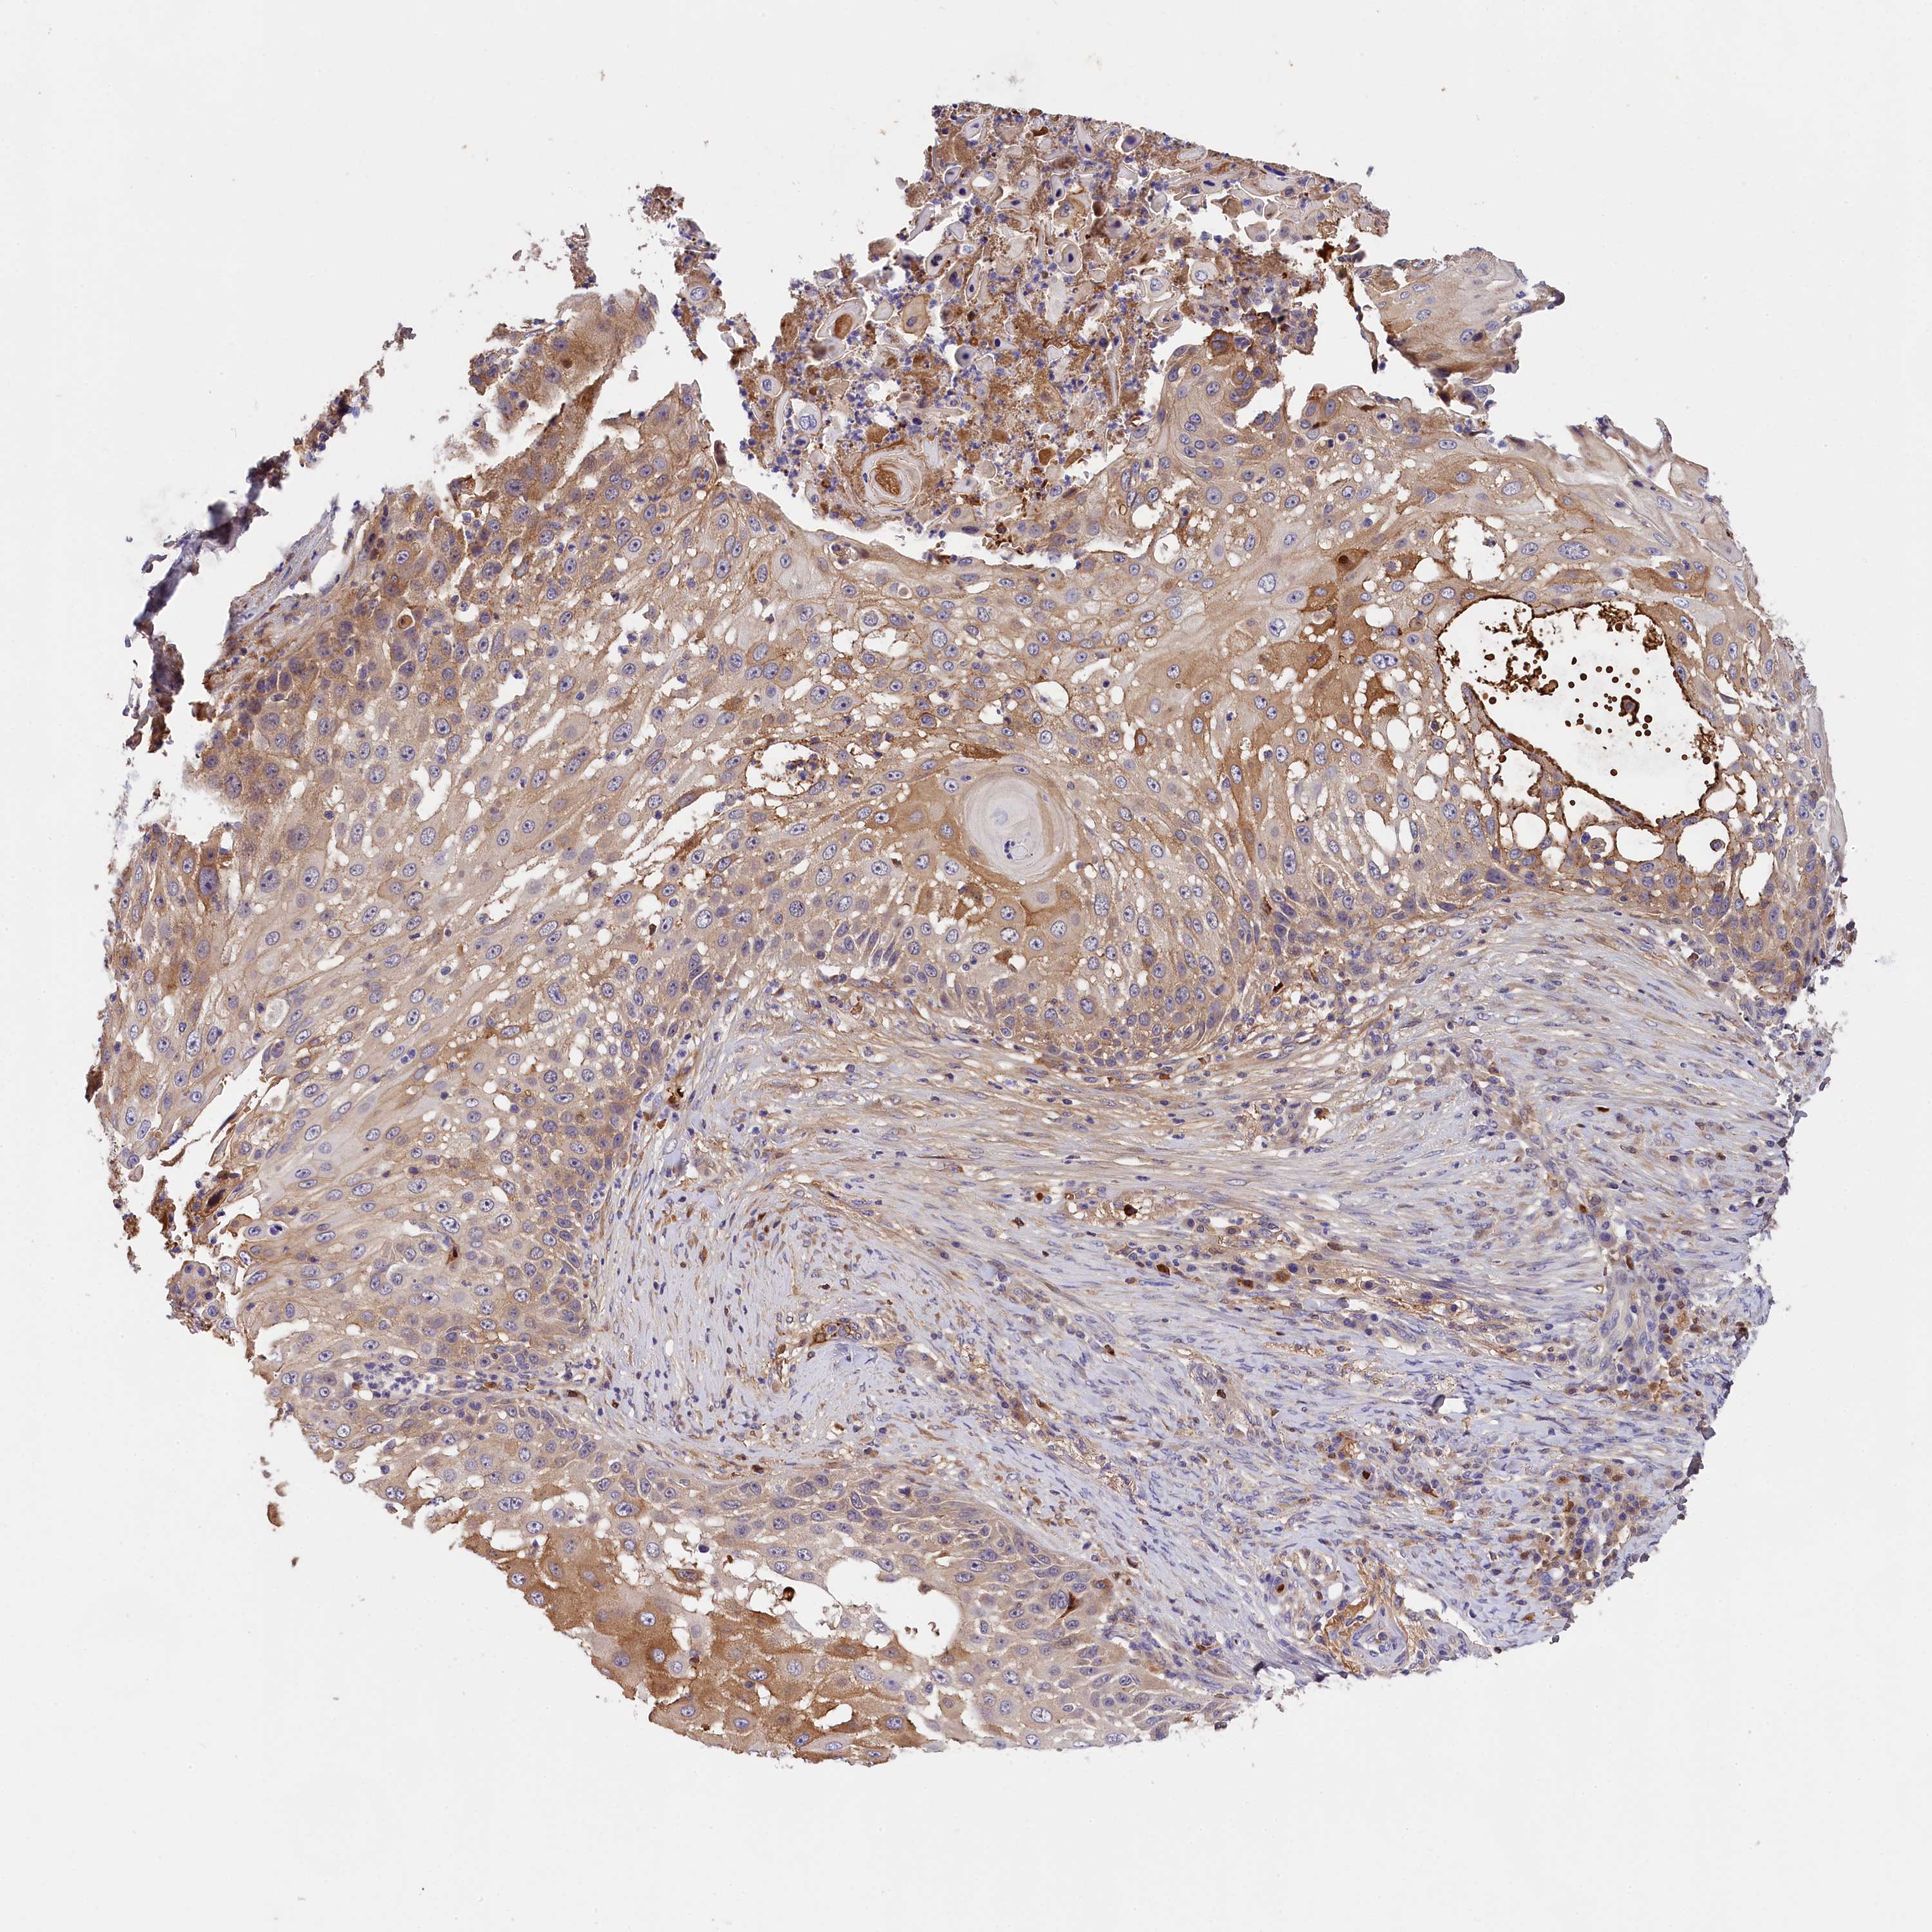

SKIN CANCER - Protein expressioni

A mouse-over function shows sample information and annotation data. Click on an image to view it in a full screen mode. Samples can be filtered based on level of antibody staining by selecting one or several of the following categories: high, medium, low and not detected. The assay and annotation is described here.

Antibody staining in the annotated cell types in the current human tissue is reported as not detected, low, medium, or high, based on conventional immunohistochemistry profiling in selected tissues. This score is based on the combination of the staining intensity and fraction of stained cells.

Each image is clickable and will lead to virtual microscopy that enables deeper exploration of all samples and also displays staining intensity scores, fraction scores and subcellular localization as well as patient and tissue information for each sample.

Antibody HPA041131

Antibody HPA041214

Basal cell carcinoma

Squamous cell carcinoma, NOS

Squamous cell carcinoma, metastatic, NOS